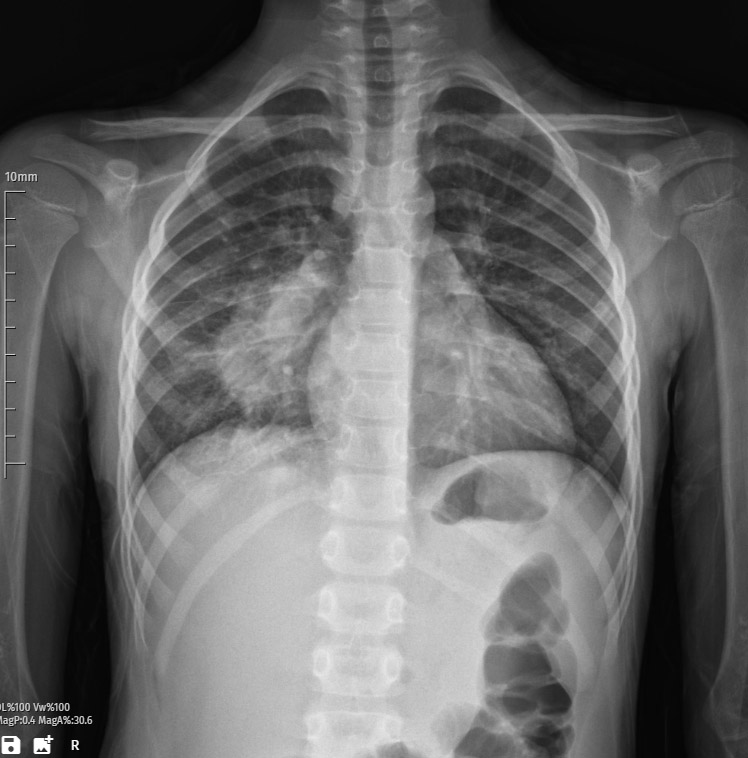

The patient’s chest X-ray reveals a consolidation image within the right lung, indicative of pneumonia. Consolidation refers to the solidification of lung tissue typically caused by infectious processes, and in this case, pneumonia is the underlying etiology.

The X-ray displays opacification and increased density in the right lung, consistent with the presence of inflammatory infiltrates. The airspaces are filled with exudate, inflammatory cells, and debris, contributing to the observed consolidation pattern. This radiographic manifestation is characteristic of bacterial, viral, or other microbial-induced pneumonia.

The consolidation is confined to the right lung, signifying a unilateral pulmonary involvement. The affected area may exhibit loss of normal lung architecture, such as air bronchograms, due to the infiltration of pathological substances.